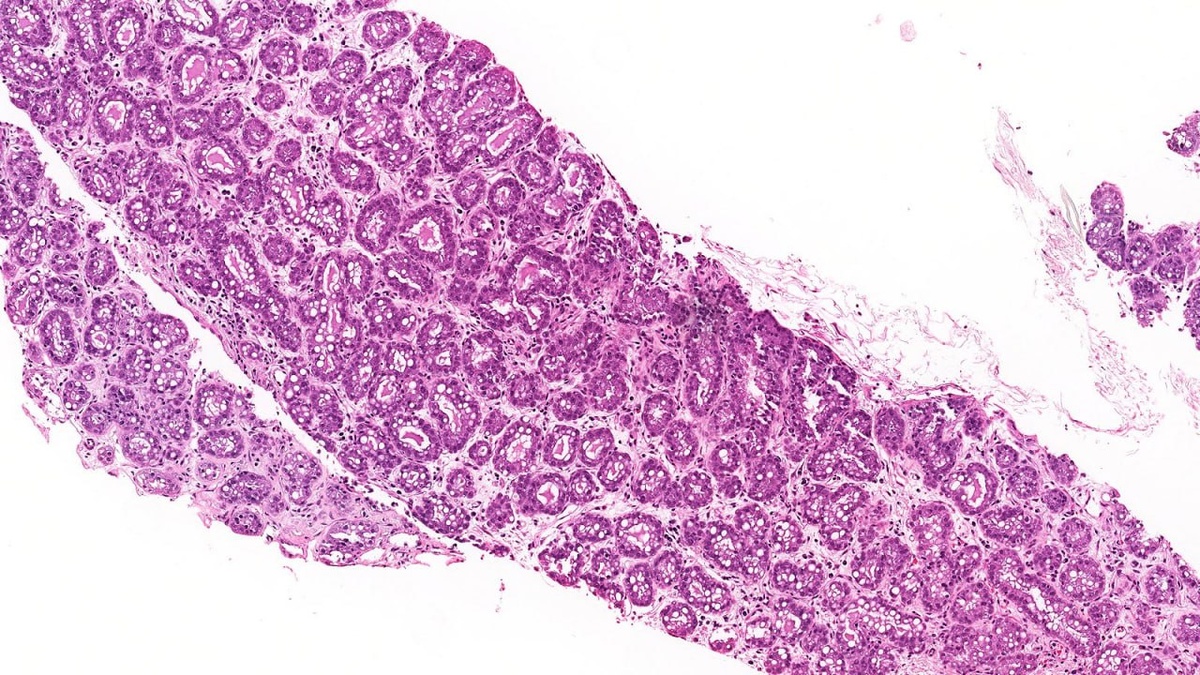

πŸ”¬ Π‘Π»ΡƒΡ‡Π°ΠΉ Π»Π°ΠΊΡ‚ΠΈΡ€ΡƒΡŽΡ‰Π΅ΠΉ Π°Π΄Π΅Π½ΠΎΠΌΡ‹ Π›Π°ΠΊΡ‚ΠΈΡ€ΡƒΡŽΡ‰Π°Ρ Π°Π΄Π΅Π½ΠΎΠΌΠ° β€” Π½Π°ΠΈΠ±ΠΎΠ»Π΅Π΅ распространённая доброкачСствСнная ΠΎΠΏΡƒΡ…ΠΎΠ»ΡŒ Ρƒ Π±Π΅Ρ€Π΅ΠΌΠ΅Π½Π½Ρ‹Ρ… ΠΈ Ρ€ΠΎΠ΄ΠΈΠ²ΡˆΠΈΡ… ΠΆΠ΅Π½Ρ‰ΠΈΠ½, состоящая ΠΈΠ· ΠΏΠ»ΠΎΡ‚Π½ΠΎ располоТСнных ΡΠ΅ΠΊΡ€Π΅Ρ‚ΠΈΡ€ΡƒΡŽΡ‰ΠΈΡ… ΠΆΠ΅Π»Π΅Π·. #молочнаяТСлСза #гистология

Π›Π°ΠΊΡ‚ΠΈΡ€ΡƒΡŽΡ‰Π°Ρ Π°Π΄Π΅Π½ΠΎΠΌΠ° β€” Π½Π°ΠΈΠ±ΠΎΠ»Π΅Π΅ распространённая доброкачСствСнная ΠΎΠΏΡƒΡ…ΠΎΠ»ΡŒ Ρƒ Π±Π΅Ρ€Π΅ΠΌΠ΅Π½Π½Ρ‹Ρ… ΠΈ Ρ€ΠΎΠ΄ΠΈΠ²ΡˆΠΈΡ… ΠΆΠ΅Π½Ρ‰ΠΈΠ½, состоящая ΠΈΠ· ΠΏΠ»ΠΎΡ‚Π½ΠΎ располоТСнных ΡΠ΅ΠΊΡ€Π΅Ρ‚ΠΈΡ€ΡƒΡŽΡ‰ΠΈΡ… ΠΆΠ΅Π»Π΅Π·.